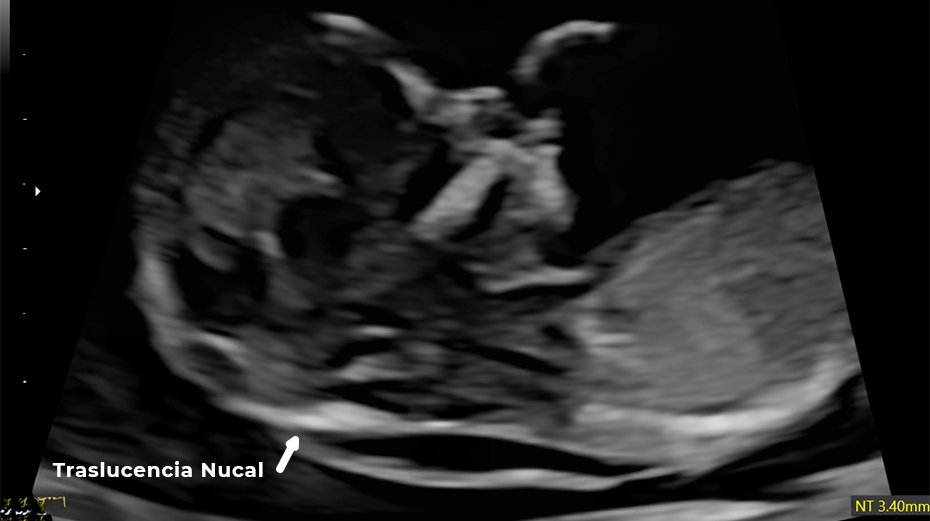

Este estudio se realiza en el primer trimestre y es clave para detectar posibles alteraciones cromosómicas como síndrome de Down, trisomía 18 y trisomía 13.

Se evalúan marcadores como:

• Translucencia Nucal

Translucencia Nucal Ductus Venoso Hueso Nasal Frecuencia Cardiaca Fetal